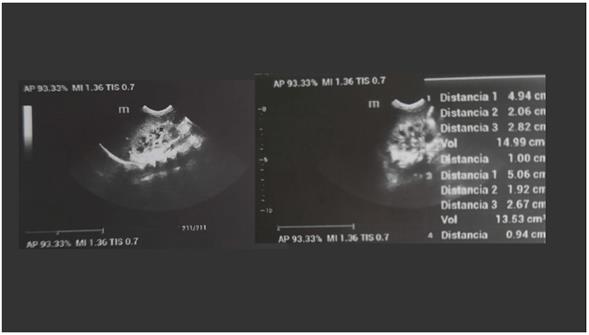

Con estos resultados, el servicio de Nefrología solicita un nuevo control que reporta: ambos riñones tienen tamaño, forma y posición normal, el derecho de 49 mm × 20 mm × 28 mm y el izquierdo de 50 mm × 19 mm × 23 mm, con parénquima de 10 mm, el cual presenta un aumento en la ecogenicidad, con buena relación seno parénquima y se identifica prominencia de los cálices, sin dilatación del sistema excretor (figura 2), con estos hallazgos se realiza el diagnóstico de megacaliosis bilateral y se solicita un renograma diurético para complementar el estudio, el cual describe una función renal conservada para ambos riñones sin evidencia de obstrucción (figura 3).

Fuente: historia clínica del paciente.

Figura 2 Ecografía renal y de vías urinarias donde se observa prominencia de los cálices sin dilatación del sistema excretor